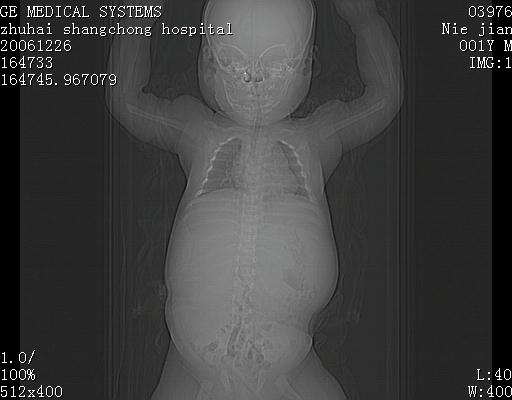

3个月婴儿腹胀来看。

【临床特点】

婴儿,腹胀,无特殊症状,未提供详细资料。

【影像特征】

1、肝明显增大,肝弥漫性低密度灶。

2、肾上腺区见类圆形肿块,其内密度不均,见片状偏高密度。

【诊断】

1、肝弥漫性病变,考虑急性肝炎致广泛脂肪浸润可能性大。

2、肾上腺区占位,假性肿瘤?肾上腺血肿(感染所致)?

楼主反馈的结果:该患儿曾在大医院看了,也劝其放弃治疗,不得已抱回家等,据说这一年中曾得过一次肺炎,做过治疗,再没别的治疗。反正一年多了还活得好好的。